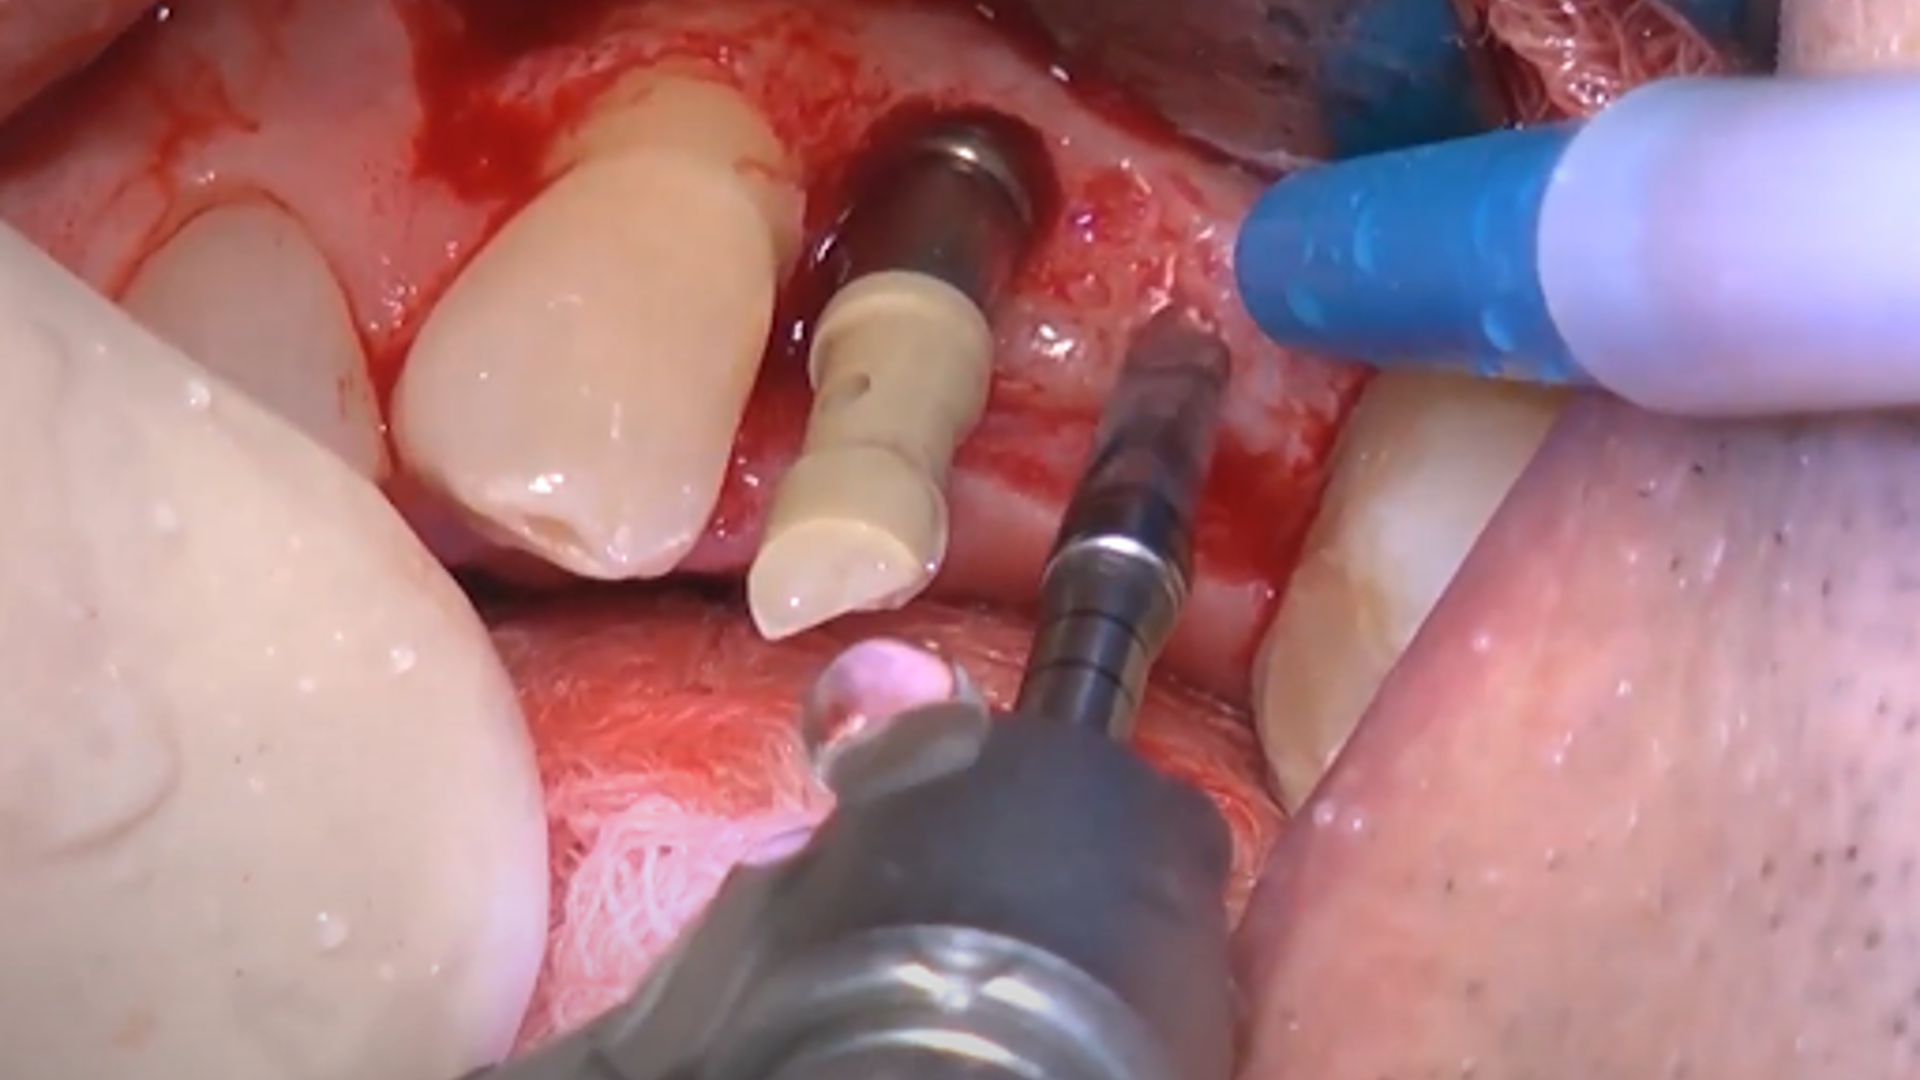

Example of different clinical cases: step-by-step surgical protocol

Osseodensification technique

Clinical video: short implants + Versah crestal sinus lift

Clinical video: Crestal sinus lift and multiple implant placement